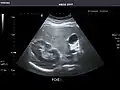

Abdominal ultrasound can be used to diagnose abnormalities in various internal organs, such as the kidneys,[1] liver, gallbladder, pancreas, spleen and abdominal aorta. If Doppler ultrasonography is added, the blood flow inside blood vessels can be evaluated as well (for example, to look for renal artery stenosis). It is commonly used to examine the uterus and fetus during pregnancy; this is called obstetric ultrasonography.[2][3]

2. ^ Whitworth M, Bricker L, Mullan C (July 2015). "Ultrasound for fetal assessment in early pregnancy". The Cochrane Database of Systematic Reviews. 2015 (7): CD007058. doi:10.1002/14651858.CD007058.pub3. PMC 4084925. PMID 26171896.

3. ^ Salomon LJ, Alfirevic Z, Bilardo CM, Chalouhi GE, Ghi T, Kagan KO, et al. (January 2013). "ISUOG practice guidelines: performance of first-trimester fetal ultrasound scan". Ultrasound in Obstetrics & Gynecology. 41 (1): 102–113. doi:10.1002/uog.12342. PMID 23280739.